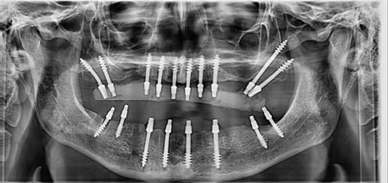

¿Qué es CorticoBasal?

El Corticobasal se reduce a una sola cirugía con colocación de prótesis definitiva en 72h. Es una cirugía muy poco invasiva, a diferencia de la implantología convencional, por lo que permite tratar con éxito pacientes especiales con patologías controladas.

Beneficia especialmente a pacientes con poco hueso, pues permite prescindir de injertos óseos y elevaciones de seno, ya que aprovecha estratégicamente el hueso remanente, por poco que sea. No obstante, se puede utilizar en todos los pacientes que necesiten un implante. La reducción del número de citas, el tiempo en consulta odontológica y el aprovechamiento del hueso del paciente sin injertos óseos ni otros biomateriales, hacen que los implantes estratégicos sean frecuentemente menos costosos que los convencionales.